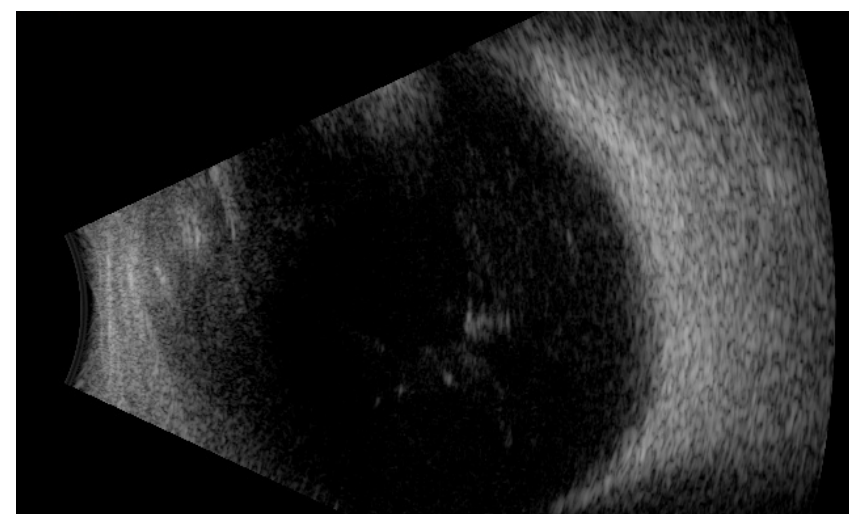

20230221164731_8455.png

图 4 左眼术后 UBM 图像。

Figure 4 The UBM in the left eye postoperative

颞侧可探及强回声光团局部与睫状突相贴 ( 图中红色箭头所示 ),其他象限没有此现象。

The UBM showed a local hyperechoic structure adherent to the ciliary process in the temporal direction in the left eye (the red arrow is shown in the figure), and other quadrants had no such phenomenon.

术后早期IOP波动于41.3~50.8 mmHg,考虑可能由少量后房出血、玻璃体积血导致(图3),给予口服和血明目片、醋甲唑胺片、卡替洛尔滴眼液、布林佐胺滴眼液止血及降眼压治疗后,玻璃体积血逐渐吸收。术后3周在局部降眼压药物控制下,IOP 波动于25.0~31.6mmHg。但术后第29天复查,左眼 IOP 30.2 mmHg,仍高于正常水平。UBM提示左眼颞侧可探及强回声光团局部与睫状突相贴,其他方位无此现象(图4)。房角镜检查:全周房角开放,小梁网色素Ⅰ级,未见虹膜周边前粘连。故考虑术后出现高眼压的原因可能是MCTR局部与睫状突接触,刺激睫状突导致房水分泌增加。遂于术后第30天,行“左眼巩膜悬吊线松解术”,术后第一天眼压即降至正常水平,随访5个月,视力0.1,-3.25/-1.00*90=0.30,眼压较稳定(16.4~19.7 mmHg),由此证明对术后高眼压原因的判断正确。

本病例中,MCTR植入术后患者出现不可控的持续性IOP升高,理论上MCTR是通过缝线固定于巩膜壁上的,较普通的CTR更加容易出现与睫状体的接触,实践中本病例的术后UBM证实MCTR局部与睫状突相贴,考虑可能是由于巩膜缝线过紧,导致了 MCTR 局部与睫状突接触,刺激睫状体,导致房水分泌过多,因此患者术后眼压一直偏高,遂行巩膜缝线松解术,术后IOP很快下降至正常且维持稳定,波动于16.4~19.7 mmHg。本病例提示了植入MCTR术后引起高眼压的重要且少见的原因,即巩膜缝合过紧引起MCTR和睫状体接触,刺激睫状突,导致房水过量分泌,从而引起术后持续性的高眼压。本病例首次报道了MCTR植入术后巩膜缝线过紧,是术后反复持续性高眼压的原因之一。